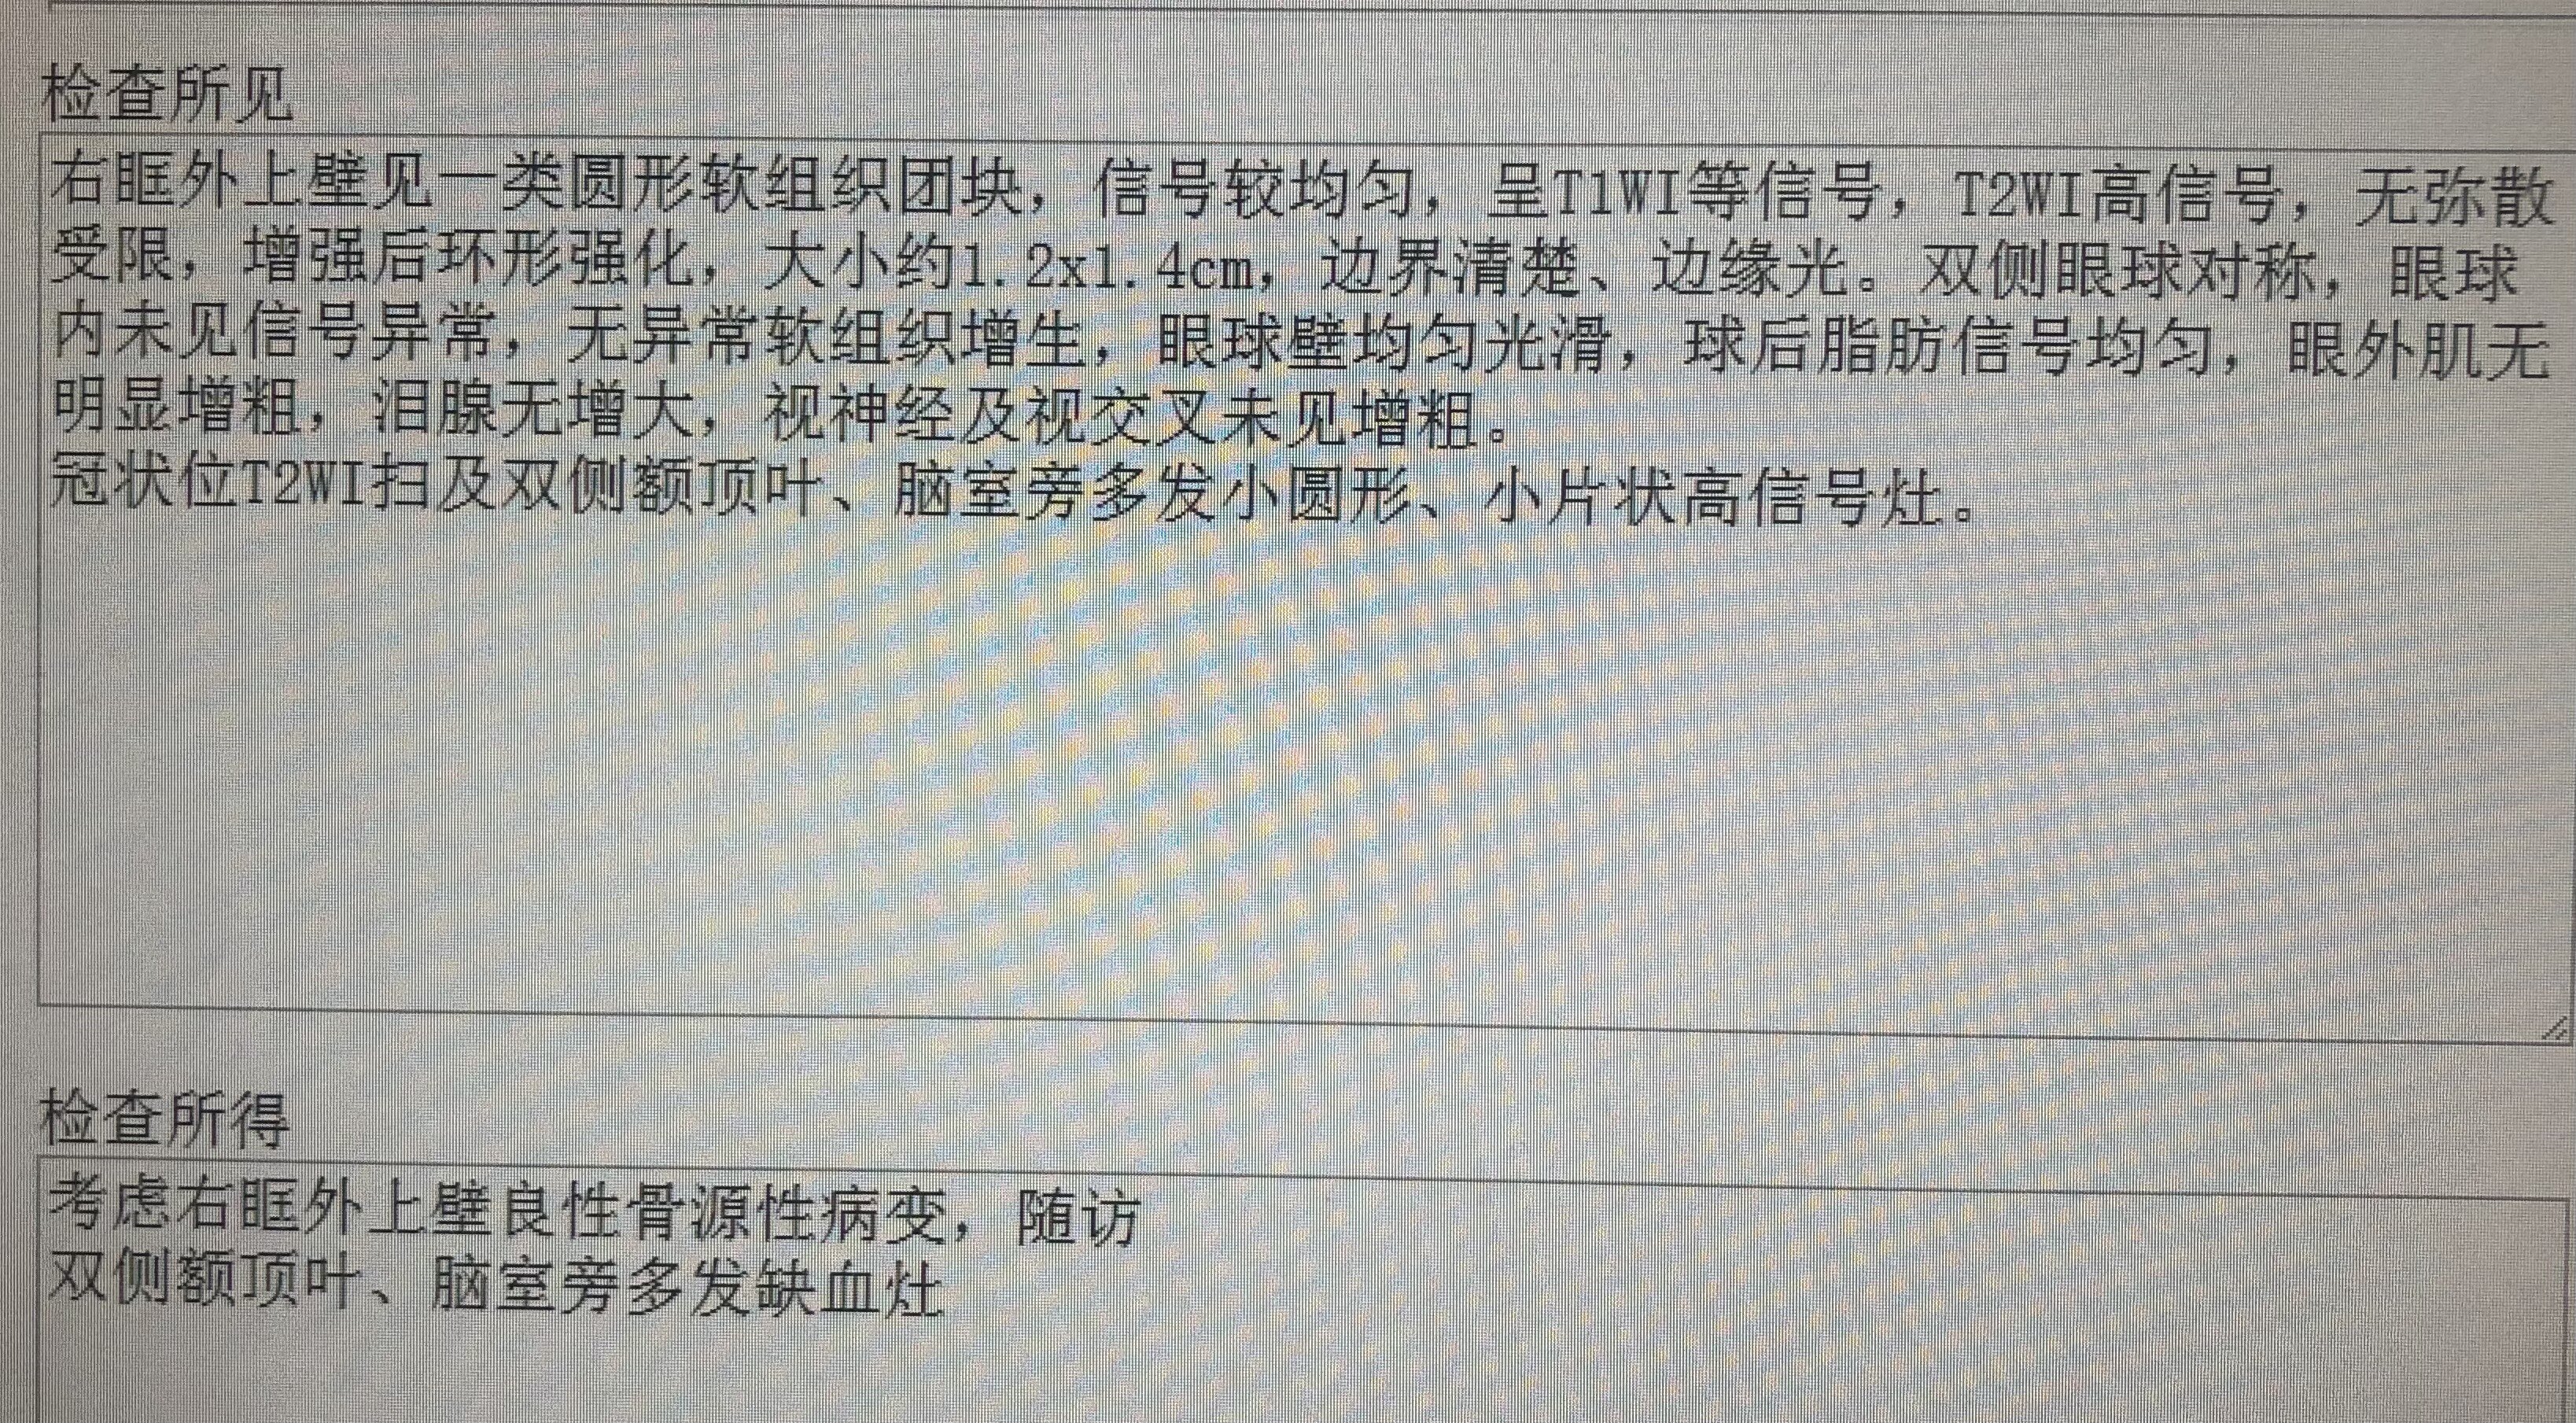

本例患者,对比双侧眼眶,可见右眼外上方骨壁增厚,骨性结构内有低信号病灶,

病灶无论在CT和核磁共振上都会显影,考虑到疼痛症状始终不缓解,最终决定手术明确性质。

核磁共振对应部位可见病变